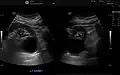

The complex cyst can be further evaluated with doppler ultrasonography, and for Bosniak classification and follow-up of complex cysts, either contrast-enhanced ultrasound (CEUS) or contrast CT is used.[13]

Renal cyst as seen on abdominal ultrasound